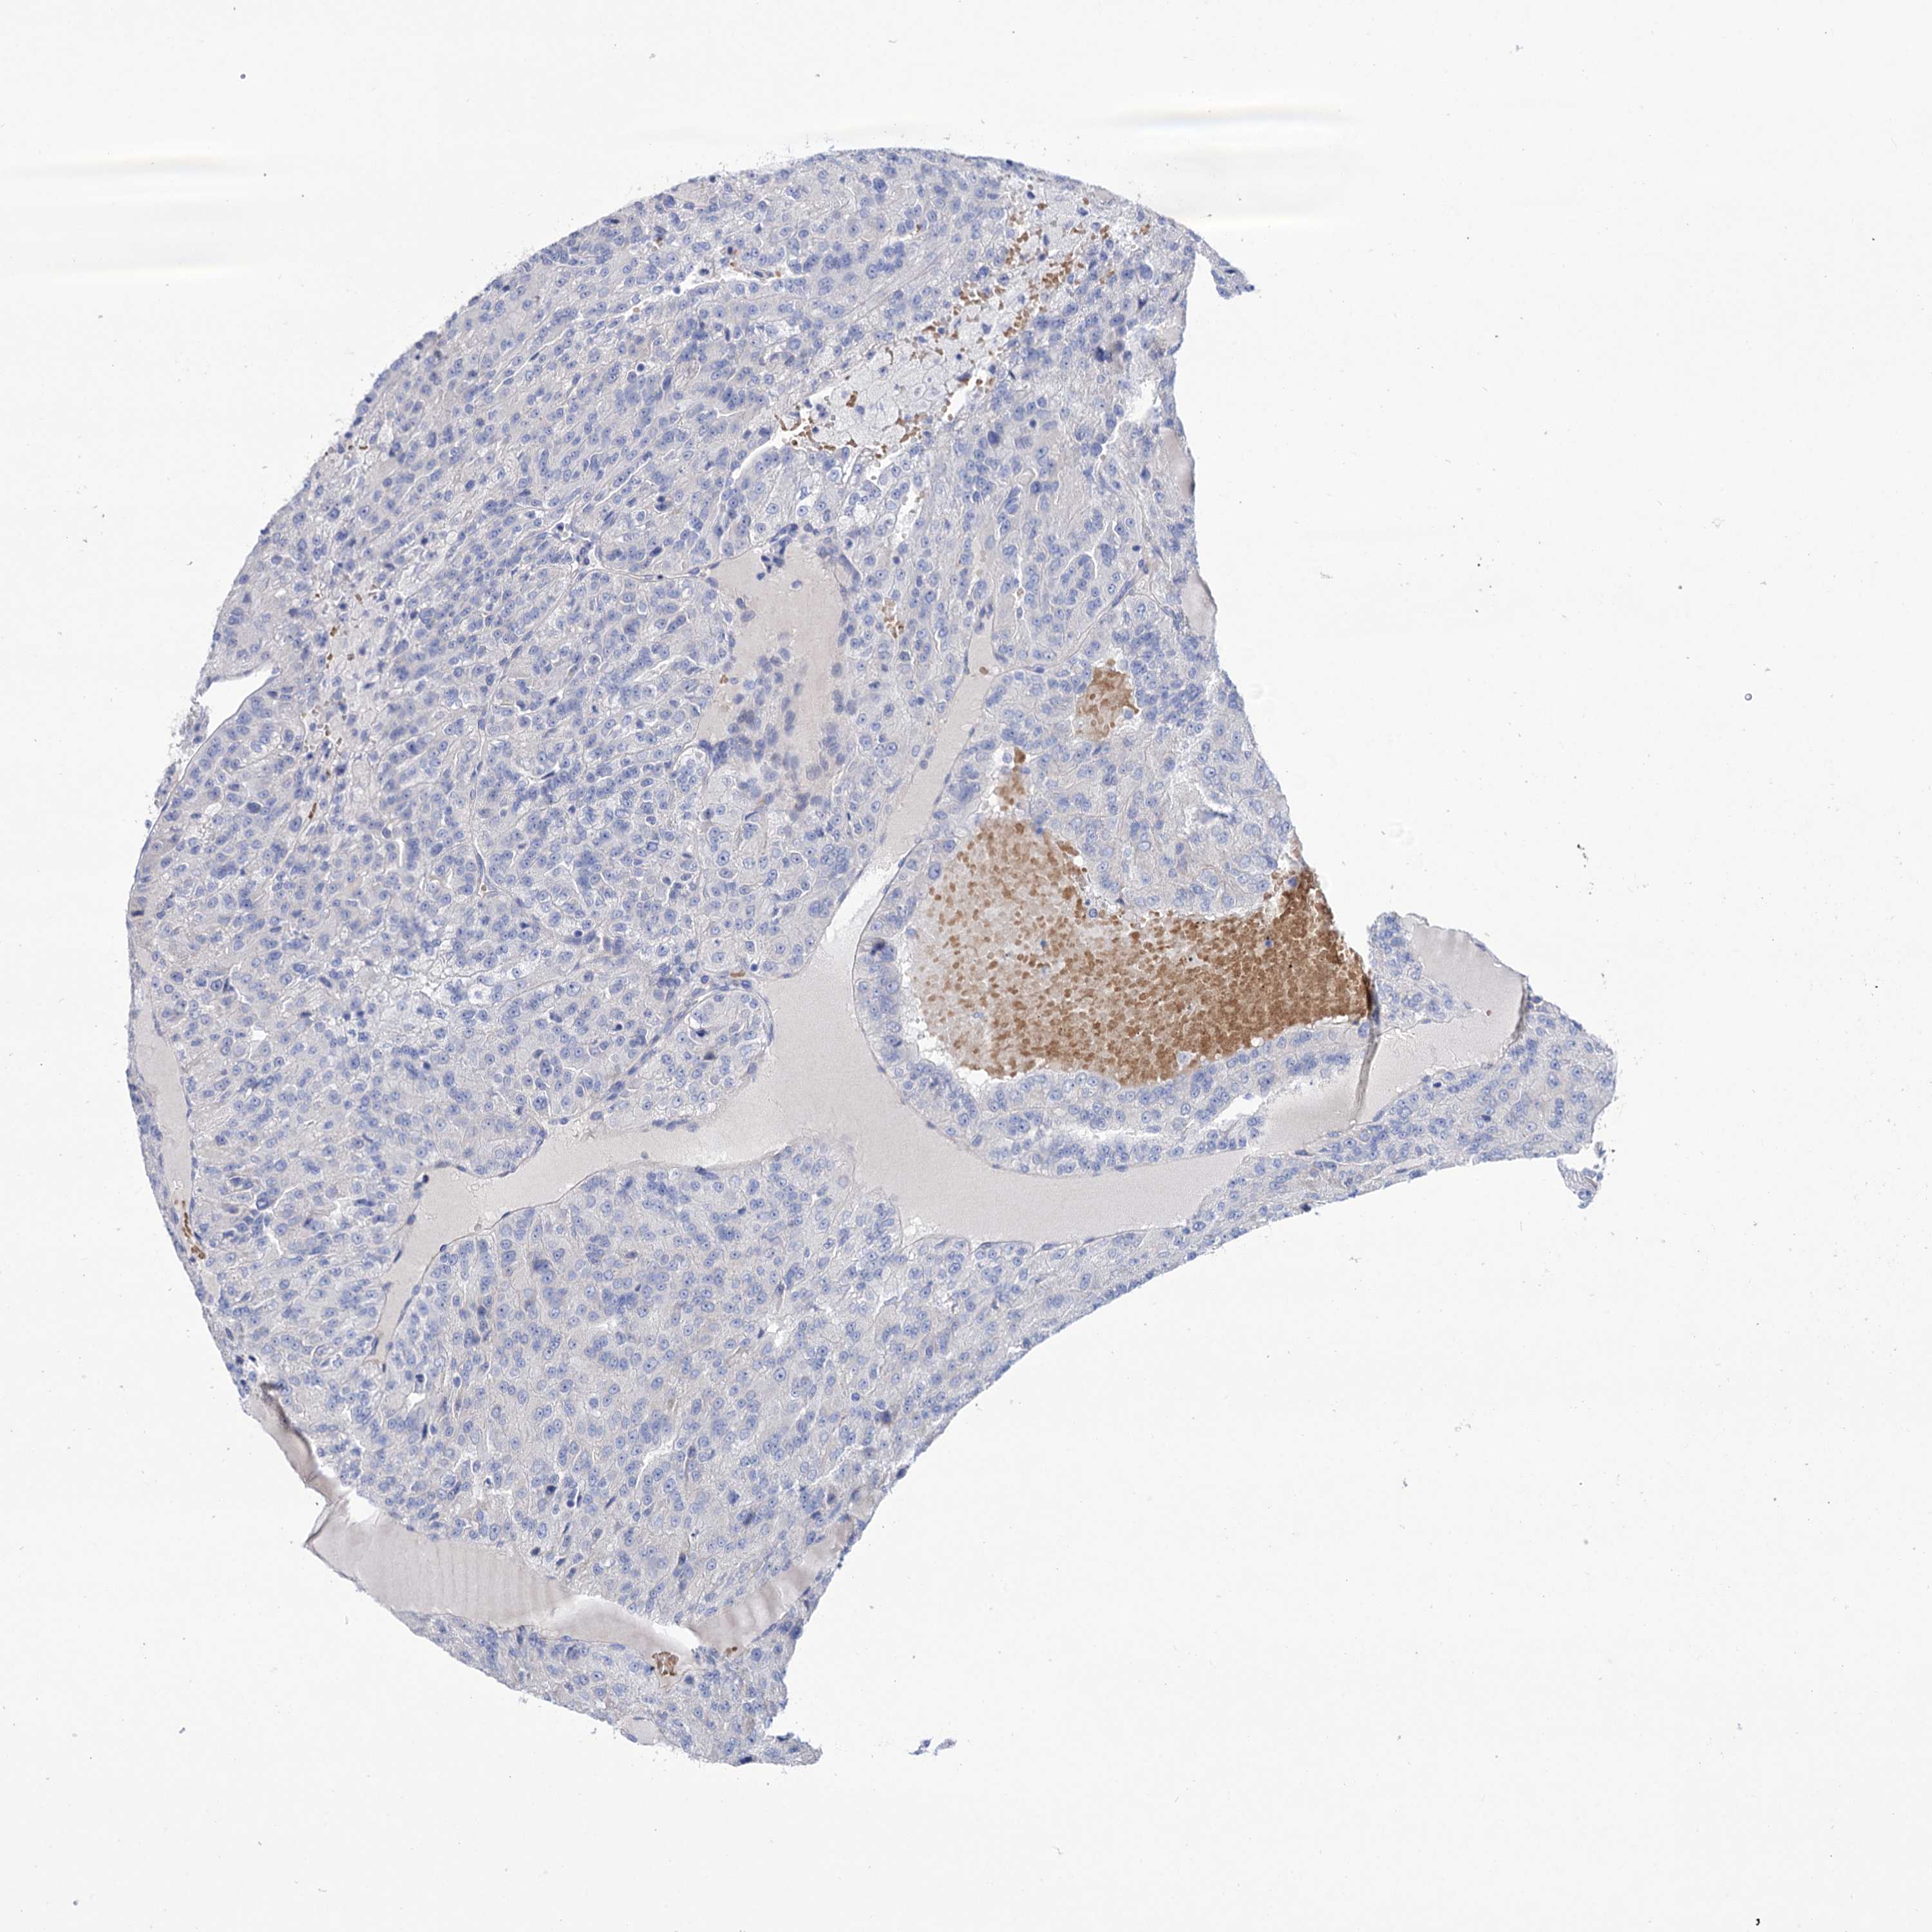

KIDNEY RENAL PAPILLARY CELL CARCINOMA (TCGA) - Interactive survival scatter ploti

The Survival Scatter plot shows the clinical status (i.e. dead or alive) for all individuals in the patient cohort, based on the same data that underlies the corresponding Kaplan-Meier plots. Patients that are alive at last time for follow-up are shown in blue and patients who have died during the study are shown in red.

The x-axis shows the expression levels (FPKM) of the investigated gene in the tumor tissue at the time of diagnosis. The y-axis shows the follow-up time after diagnosis (years). Both axes are complimented with kernel density curves demonstrating the data density over the axes. The top density plot shows the expression levels (FPKM) distribution among dead (red) and alive patients (blue). The right density plot shows the data density of the survived years of dead patients with high and low expression levels respectively, stratified using the cutoff indicated by the vertical dashed line through the Survival Scatter plot. This cutoff is automatically defined based on the FPKM cutoff that minimizes the p-score. The cutoff can be changed by dragging the vertical line or by entering a cutoff value in the square labeled "Current cut-off".

Under the Survival Scatter plot the p-score landscape (black curve; left axis) is shown together with dead median separation (red curve; right axis). Dead median separation is the difference in median mRNA expression between patients who have died with high and low expression, respectively. It is calculated as follows: median FPKM expression of dead patients with high expression - median FPKM expression of dead patients with low expression. This is intended to aid the user in visually exploring custom cutoffs and the associated p-scores and dead median separation.

Individual patient data is displayed and can be filtered by clicking on one or more of the category buttons on the top of the page. Categories describing expression level and patient information include: high, low, alive, dead, female, male and tumor stages. The scale of the x-axis can be toggled between linear and log-scale by clicking on the "x log" button. Mouse-over function shows TCGA ID, patient information and mRNA expression (FPKM) for each patient.

& Survival analysisi

Kaplan-Meier plots summarize results from analysis of correlation between mRNA expression level and patient survival. Patients were divided based on level of expression into one of the two groups "low" (under cut off) or "high" (over cut off). X-axis shows time for survival (years) and y-axis shows the probability of survival, where 1.0 corresponds to 100 percent.

YARS2 is not prognostic in Kidney Renal Papillary Cell Carcinoma (TCGA)

Best expression cut offi

Based on the FPKM value of each gene, patients were classified into two groups and association between prognosis (survival) and gene expression (FPKM) was examined. The best expression cut-off refers the FPKM value that yields maximal difference with regard to survival between the two groups at the lowest log-rank P-value. Best expression cut-off was selected based on survival analysis .

When clicking on this number, the vertical dashed line indicating cut-off, the interactive survival plot, and the Kaplan-Meier curve will be adjusted to show results based on the best expression cut-off.

: 9.27